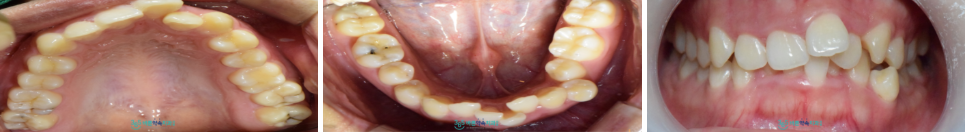

오늘 소개해 드릴 환자분께서는

20대 여성분으로

위아래 앞니가 많이 삐뚤빼뚤하여

교정을 하고 싶다고

말씀을 해주셨는데요.

먼저 구강 내를 확인해 보았더니

앞니가 총생이 심한 상태였는데요.

치아 총생이란

치아가 정상적인 위치에 있지 않고

치열이 뒤틀리면서

삐뚤빼뚤하게 겹친 상태로

자리 잡고 있는 것으로

턱뼈의 크기에 비하여

치아의 크기가 크거나

잇몸뼈의 공간 부족으로 인해

치아 총생이 주로 나타나는데요.